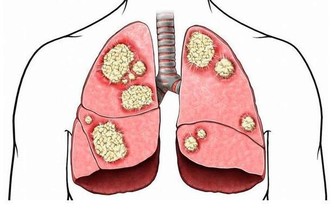

***3.有益心臟。***人在下蹲的時候,有利於氣血流暢,心肺血流量相對充沛,可緩解動脈硬化、降低血脂,還可減少冠心病和腦中風的發病率;下蹲還能加大胸腔和肺的活動範圍,從而改善我們的心肺功能。